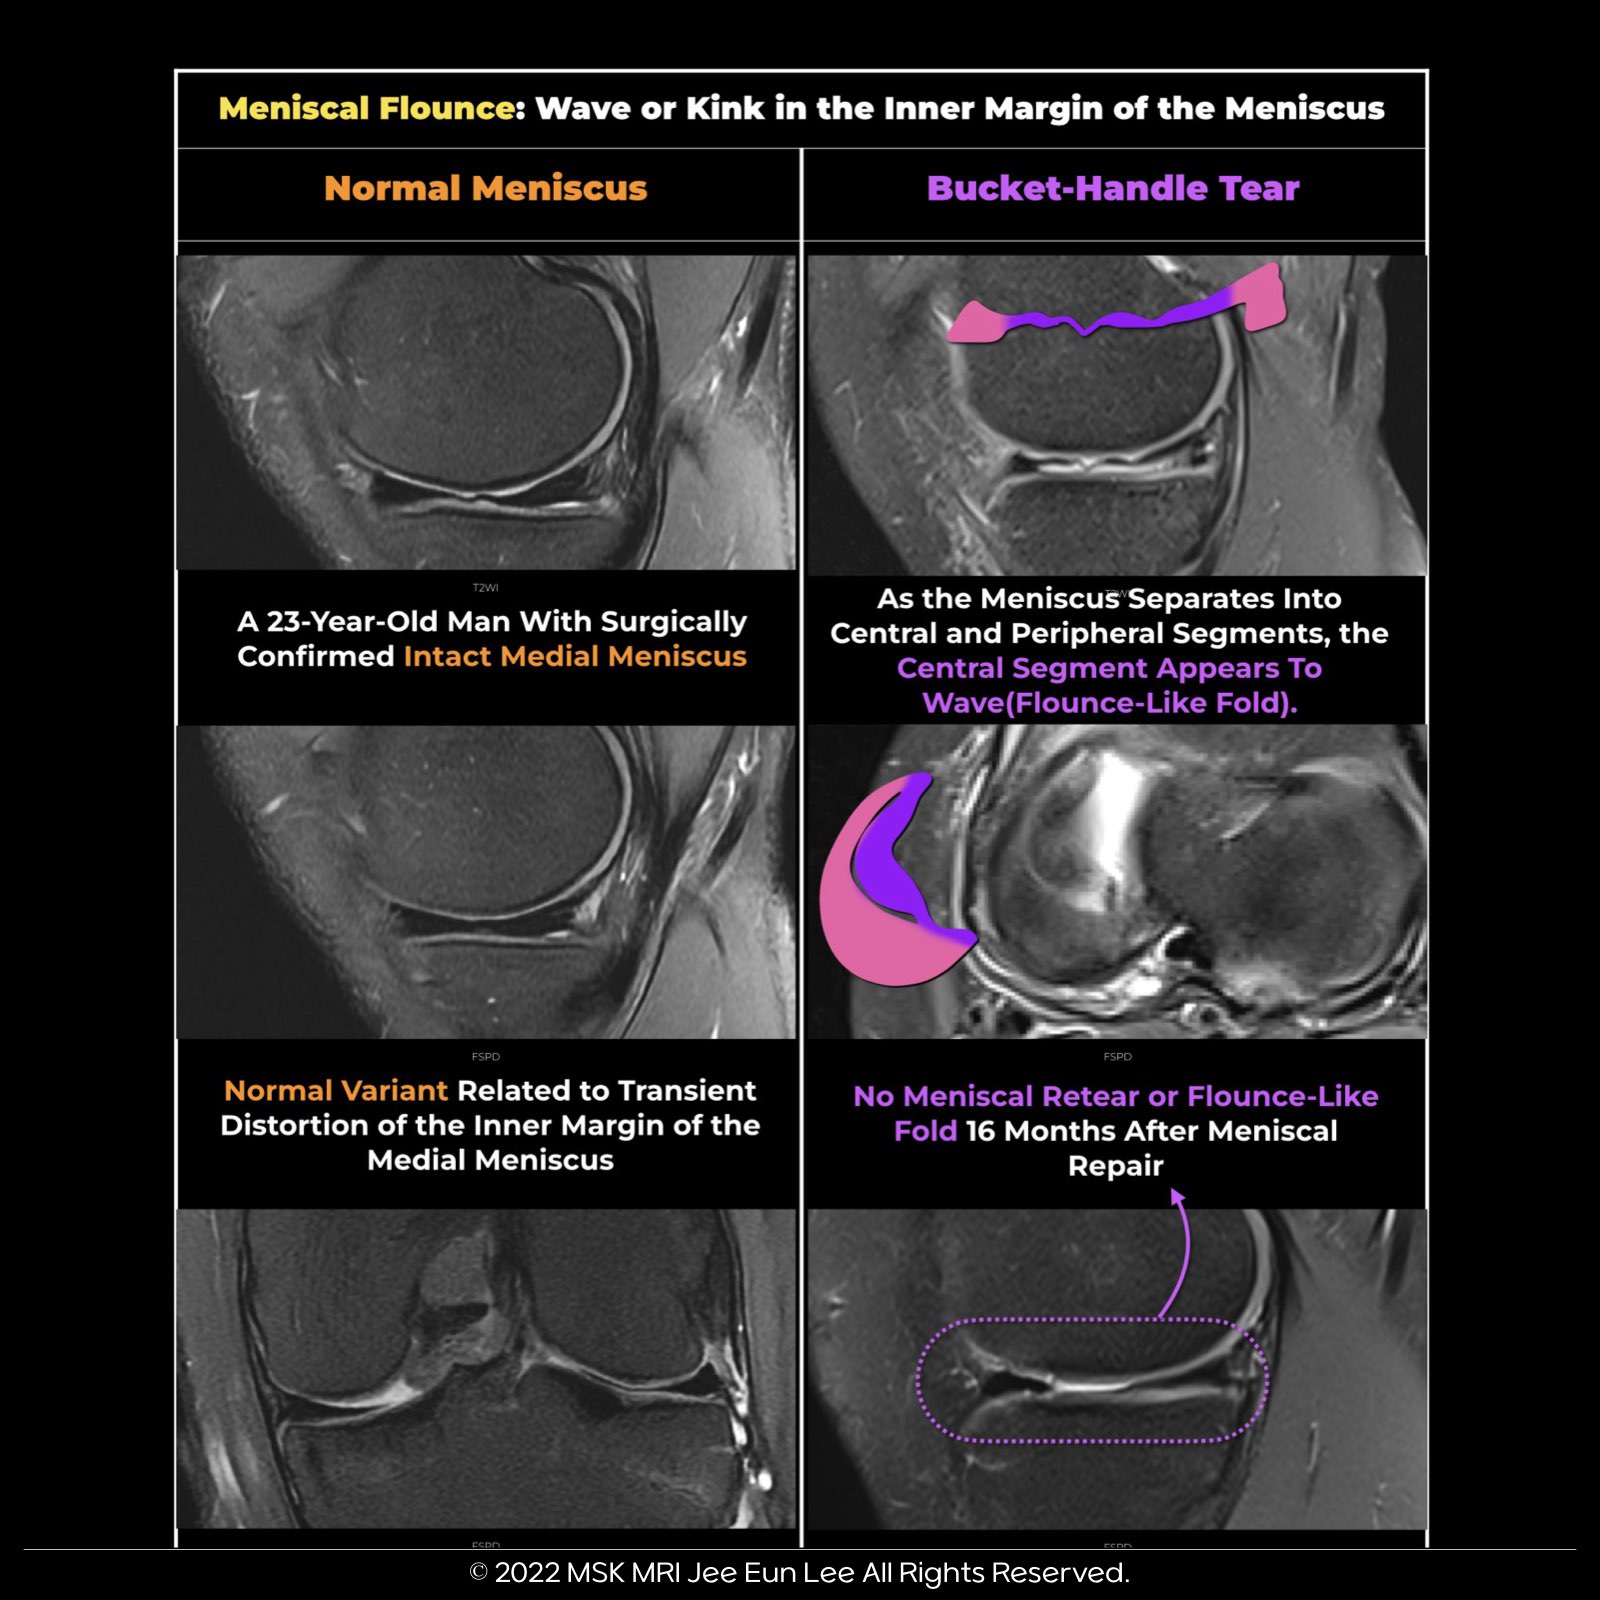

✅ Meniscal Flounce Summary:

- Meniscal flounce refers to a wave-like appearance of meniscus edges in sagittal MRI images.

- It occurs in about 0.2% to 0.3% of patients, mainly when the knee is flexed, and the free edge shows redundancy.

- While discussed in the context of the medial meniscus, it can also affect the lateral meniscus.

- The wave-like appearance is notable, but other attachments are usually intact, and no tearing is seen in coronal images.

✅ Pitfall:

- Flounce may mimic a torn meniscus in sagittal images but is not indicative of an actual tear.

- Coronal images can make the free edge look torn due to the wave-like shape.